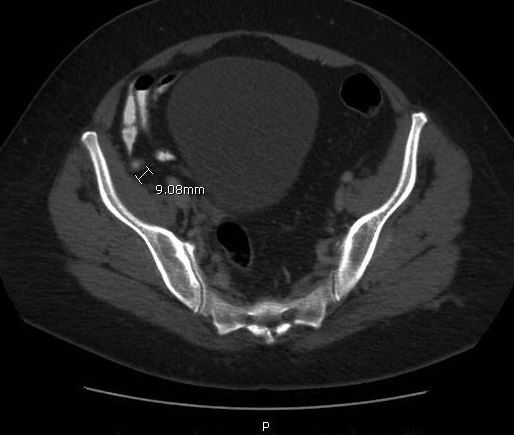

A computed tomography (CT) scan of the abdomen and pelvis with oral and intravenous contrast identified contrast in the base of the appendix but not the tip (Figures). The tip appeared mildly thickened, measuring approximately 6 to 9 mm, with hazy infiltrative change adjacent to it. Numerous clustered subcentimeter lymph nodes in the right lower quadrant also were identified, making the diagnosis consistent with acute appendicitis.